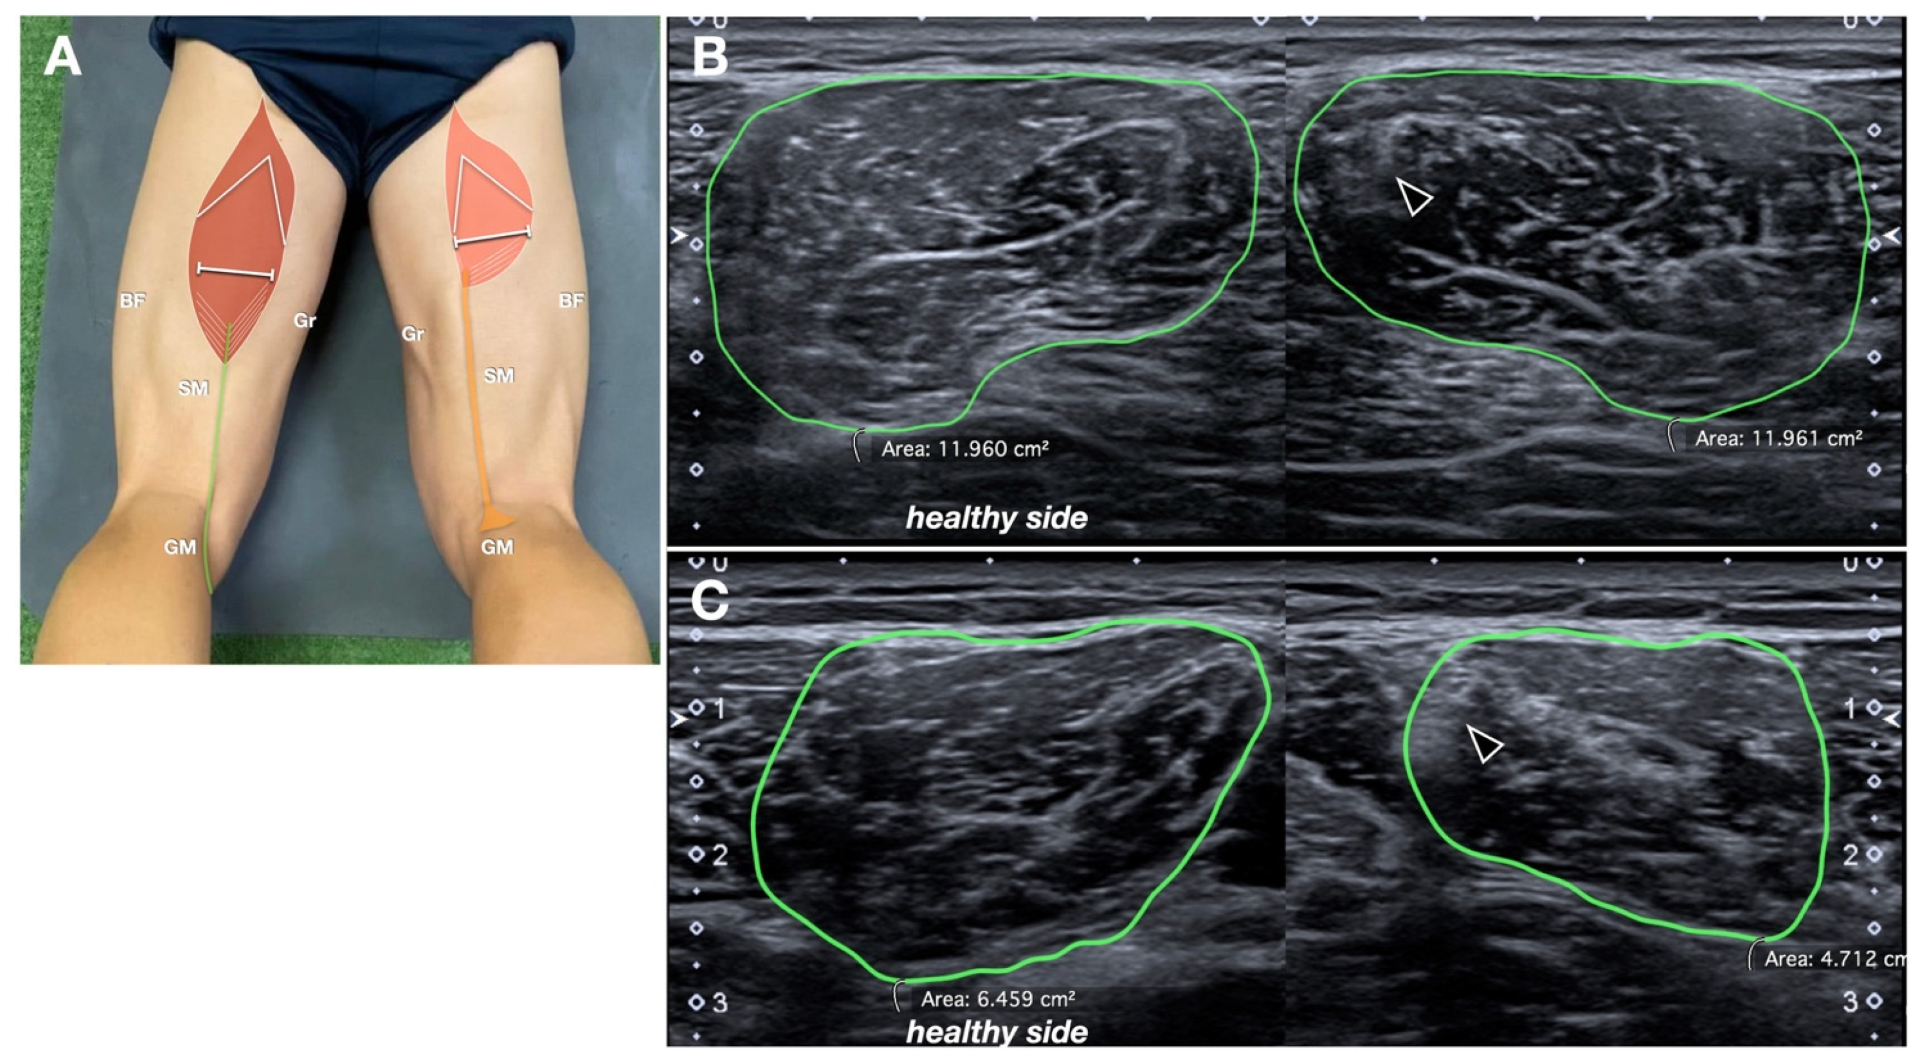

Figure 6.

Semitendinosus muscle CSA ratio. (A) Schematic drawing (same as Figure 1B, refer to it for the abbreviations) indicating probe position. (B,C) Comparative axial sonograms in two different patients. The margins of the semitendinosus muscles are manually traced (in green) to obtain the corresponding CSA. In (B), the CSA is similar between the two sides, with only some mild echostructural alteration along the intramuscular tendon (black arrowhead) of the semitendinosus muscle. In (C), the CSA is reduced more evidently.

The cross-sectional area (CSA) of the ST muscle belly was measured bilaterally, at the middle third of the thigh, using axial sonograms, with measurements compared to the contralateral side (Figure 6). To ensure reproducibility, the CSA was measured at the level where the intramuscular raphe of the ST, a reliable anatomical US landmark for the identification of the muscle, was no longer visible (just caudal to it) [14]. The muscle CSA ratio was calculated similarly to the tendon CSA ratio.